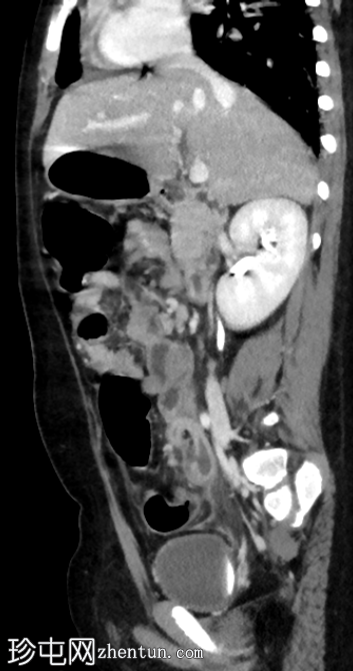

CT

冠状位增强扫描(门静脉期)

阑尾扩张,壁增厚并强化,周围阑尾周围脂肪组织条索状改变。

阑尾尖端近端可见局灶性壁缺损。

该缺损旁可见一小环状强化积液。

结肠周围及肠系膜区可见多个肿大淋巴结。

腹膜增厚。

影像

学表现符合急性阑尾穿孔的诊断,阑尾尖端近端可见局灶性壁缺损。环状强化积液提示阑尾周围脓肿。

术中发现证实了影像诊断,阑尾发炎,阑尾尖端近端有壁缺损,阑尾周围区域有脓液积聚。